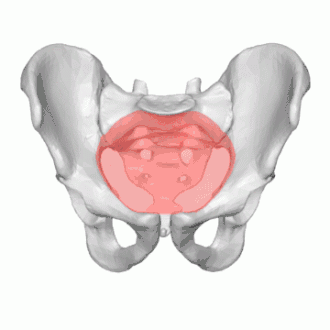

Diameters of superior aperture of lesser pelvis (female)

Its position and orientation relative to the skeleton of the pelvis is anatomically defined by its edge, the pelvic brim. The pelvic brim is an approximately apple-shaped line passing through the prominence of the sacrum, the arcuate and pectineal lines, and the upper margin of the pubic symphysis.

The edge of the pelvic inlet (pelvic brim) is formed as follows:

Anteriorly

by the pubic crest (or pubic symphysis)

Laterally

by the iliopectineal line

Posteriorly

by the anterior margin of the base of the sacrum (or the ala of sacrum) and sacrovertebral angle (or sacral promontory)